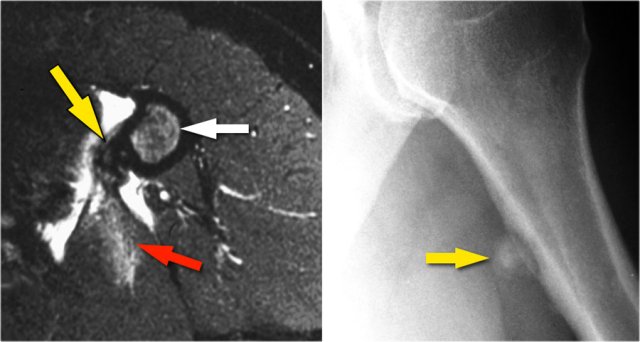

Arthrosis in valgus overload syndrome

Due to the valgus overload there are shear forces on the posteromedial part of the humeroulnar joint.

Notice the subchondral sclerosis seen on the T1W-image (red arrow).

On the T2W-image there is subchondral bone marrow edema and cartilage loss (yellow arrow).

These are images of a 20 year old baseball pitcher.

Scroll through the images.

On the coronal images there is a beautiful anterior bundle of the UCL, but notice that there is osteophyte formation on the medial part of the joint (red arrow).

As we go further posteriorly there is a small area of low signal intensity (yellow arrow), which is an avulsion of part of the UCL.

This is better appreciated on the radiograph.

Continue with the axial scan.

As we look on the axial scan, we can appreciate the huge osteophyte formation.

Notice that the ulnar nerve (blue arrow) is next to these osteophytes and these patients may present with ulnar neuropathy.